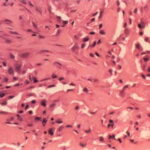

Epithelioid sarcoma = ورم عفلي بشرواني